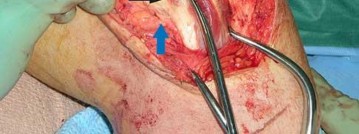

Tarsal coalitions occur when primitive mesenchymal cells fail to differentiate and form the

normal articular separations between the tarsal bones of the hindfoot. Overall incidence is difficult to determine because many affected people are minimally symptomatic or asymptomatic. Symptomatic tarsal coalitions typically present in adolescents as a painful flatfoot; however, there are a number of possible presentations, and occasionally symptoms do not appear until adulthood. Most tarsal coalitions are between the calcaneus and the navicular (CN) and the talus and the calcaneus (TC). Although most TC coalitions are across the middle facet, posterior facet coalitions do occur. Plain radiographic evaluation of suspected tarsal coalition is the mainstay for diagnosis. However, coalitions can be bony or fibrous, and making the diagnosis can be difficult. The addition of CT images to distinguish bony definition and MR images to decipher soft tissue can aid in diagnostics. Bony coalitions appear as definite bony bridging between the bones, while fibrous coalitions are suspected when distortion of the bony anatomy is seen. Bony coalitions are best seen on the oblique view (CN) and Harris axial view (TC). There are a number of secondary signs such as the anteater (AE) sign (elongation of the anterior process of the calcaneus as it extends to the navicular as seen on the lateral view [CN]). talar beaking (traction spur of the talar neck thought to result from abnormal stresses as seen on the lateral view [both CN and TN]), and the “C” sign (a continuous cortical contour from the medial talus to the sustentaculum tali [ST]) as seen on the lateral view (TC). A number of newer signs are not as well known, such as a broad mediolateral dimension of the navicular on the anteroposterior (AP) view (the

navicular is wider than the talar head [CN]), nonvisualization of the middle facet on the lateral view (TC), the brick sign (a normal ST is flat, but a distorted ST is enlarged and curved [CN]), and a tapered lateral navicular bone as seen on the AP view (the medial navicular [CN] is much thicker than the lateral navicular).

Figure 1a shows talar beaking (TB), an AE, and an open middle facet (MF). Figure 1b shows a wide navicular (WN), and Figure 1c shows an abnormal articulation between the calcaneus and the navicular, all consistent with a CN coalition.